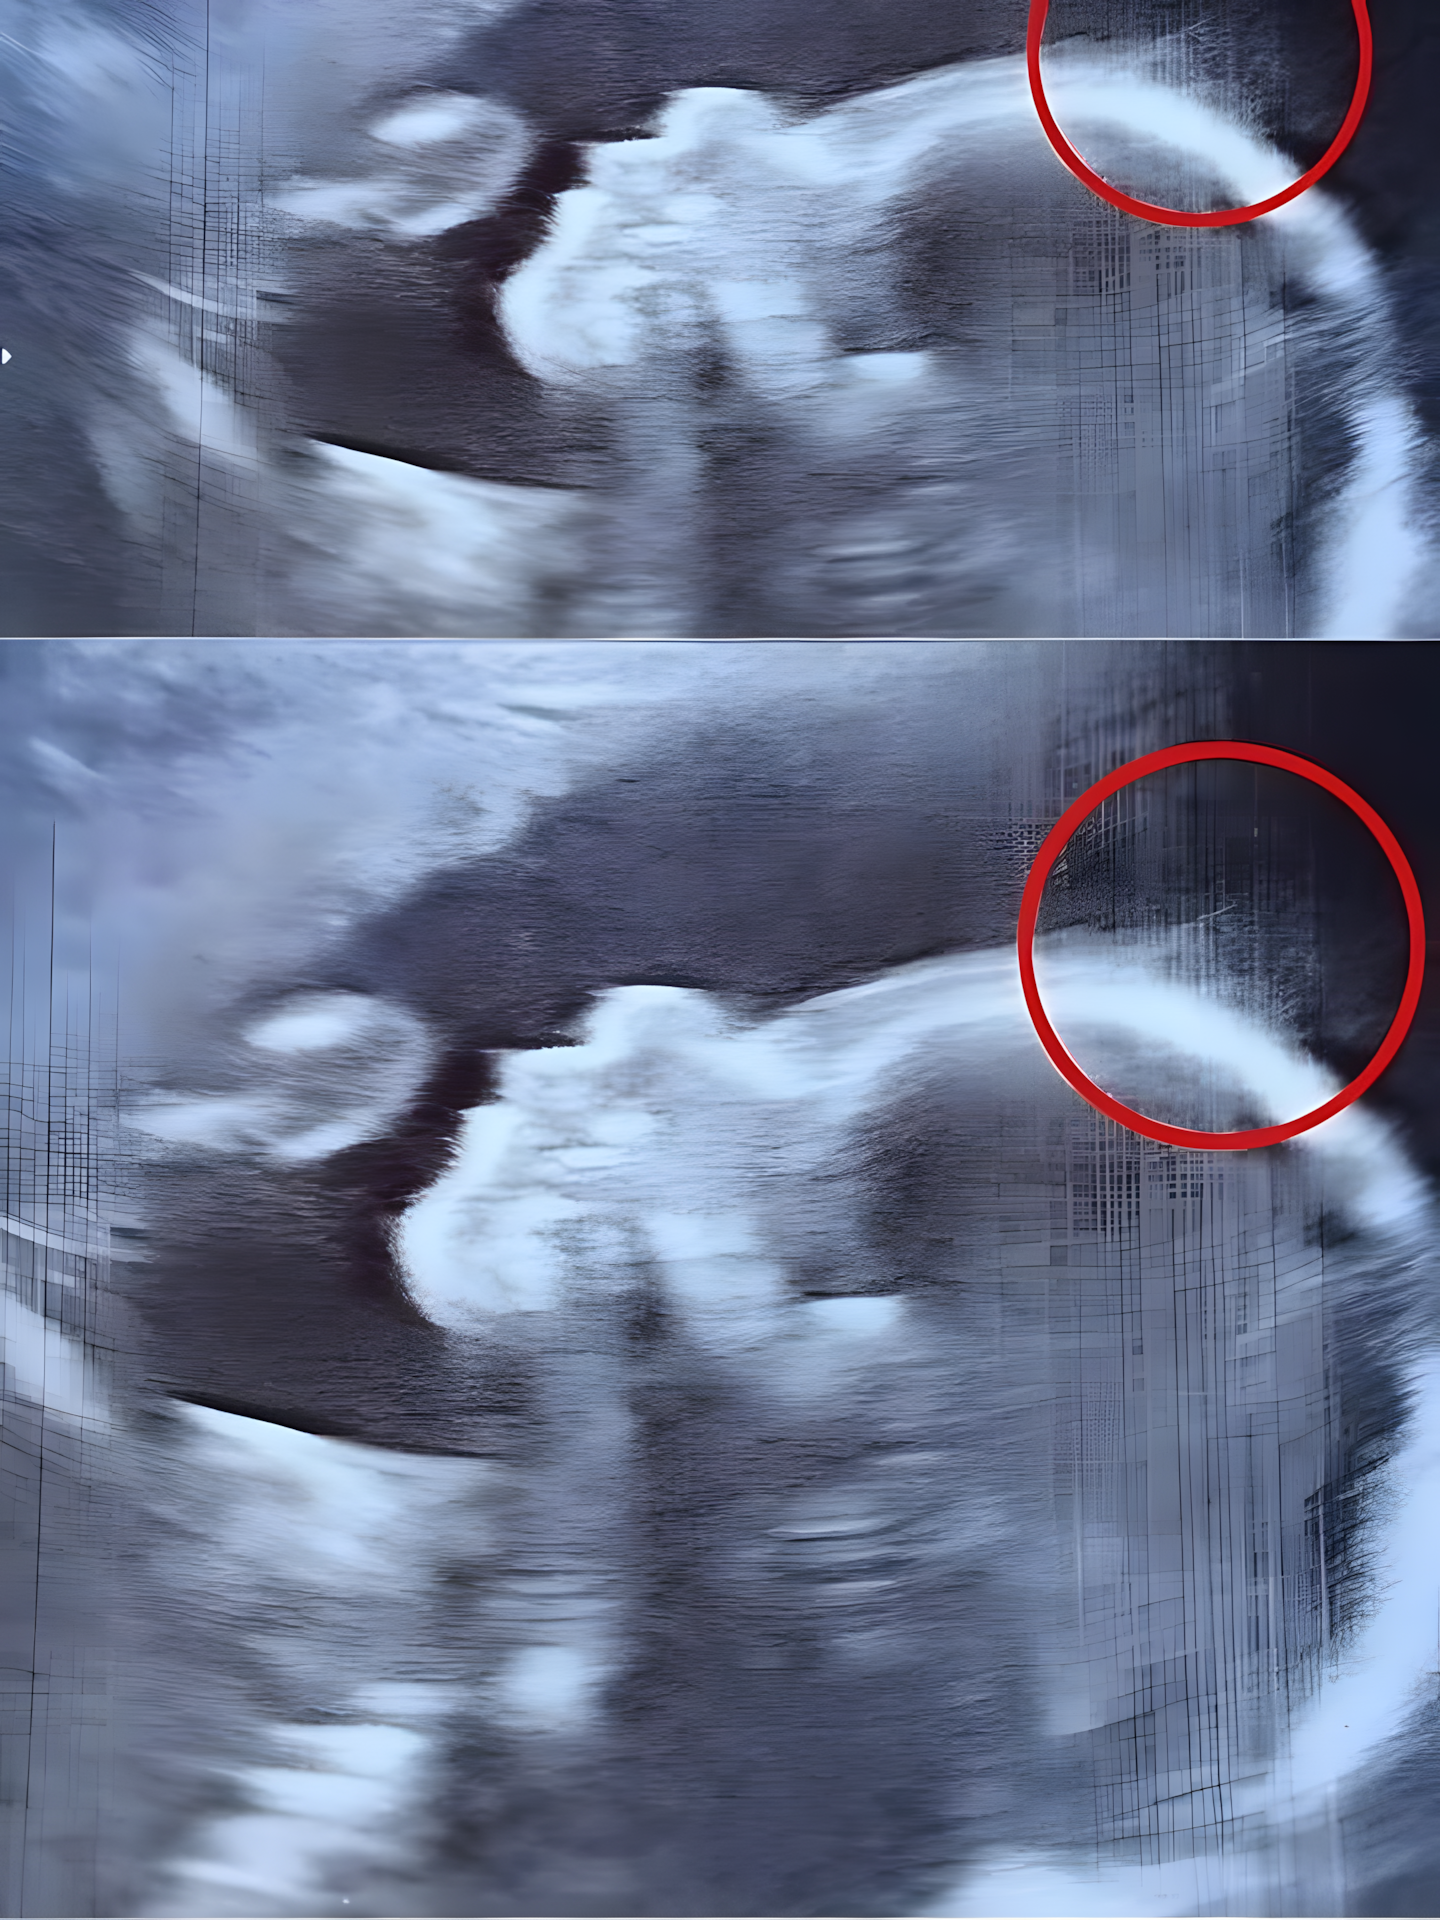

Tijdens deze routinecontrole merkte het medische team iets vreemds op de foto op. Na even nadenken beseften ze dat het geen schaduw of technisch artefact was… maar haar! Ja, haar zichtbaar op de echo – een zeer zeldzame gebeurtenis in dit stadium van de zwangerschap.

Op dat moment fantaseerde Natasha al over een klein meisje met een paar wilde lokken. Maar ze had geen idee wat haar te wachten stond…